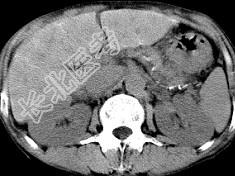

- 单项选择题男,40岁有血吸虫感染史, 腹胀不适,食欲减退, CT扫描所见如图,最可能诊断为 ( )

A、脂肪肝

B、肝炎后肝硬化

C、血吸虫后肝硬化

D、酒精性肝硬化

E、胆汁性肝硬化